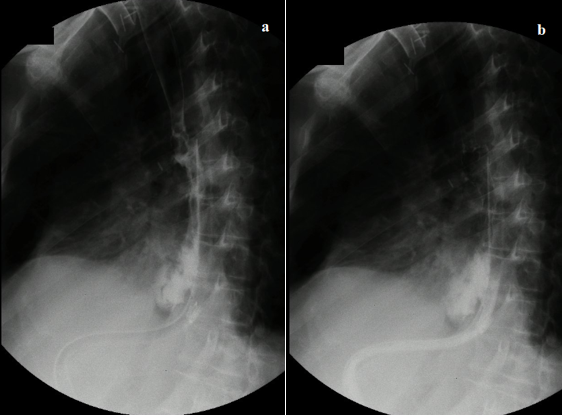

A 68-year-old man with a history of gastroesophageal junction carcinoma underwent neoadjuvant chemotherapy and subsequent radical esophagectomy. Post-surgery, the patient developed empyema, and an esophagogastric anastomotic leakage was suspected. Revision surgery revealed no clear leakage but pleurectomy and decortication were performed. Esophagogastroduodenoscopy confirmed an anastomotic leakage covering 40% of the anastomotic end (Figure 1), extending into the mediastinum. Another endoscopy identified leakage compromising approximately 50% of the anastomotic end. A 15 cm lumen-apposing metal stent (LAMS) was inserted, and the patient received antibiotics, enteral nutrition, and was placed on nil per os (NPO) status. Two months later, the LAMS was removed, but two persistent leakage sites were found (Figure 2a). A new LAMS was inserted along with the ENDOVAC system using GranuFoamTM (Figure 2b). The E-VAC system was changed every 3-5 days for a month, totaling 7 replacements. During one replacement, upper gastrointestinal bleeding occurred and was managed with hemoclips. The patient underwent endoscopy again, revealing a persistent 3 mm leak. A new E-VAC system was positioned and replaced twice. Subsequent endoscopy showed no leakage, and the patient continued with the previous LAMS and enteral nutrition through jejunostomy.

Figure 2a LAMS positioned with adjacent granulation tissue, *shows persistent anastomotic leakage. 2b GranuFOAMTM manually prepared for insertion with E-VAC system.